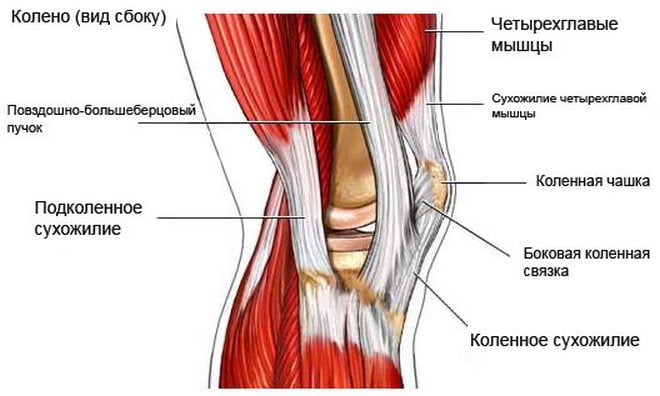

Иначе болезнь именуют «коленом прыгуна». Обусловлено это тем, что чаще всего она поражает людей, занимающихся велоспортом, баскетболом, волейболом и другими «прыгучими» видами спорта. Патология характеризуется поражением связки надколенника, которая крепится к большеберцовой кости и является продолжением связки четырехглавой бедренной мышцы. Она отвечает за разгибание коленки и подъем конечности в вытянутом виде.

В большинстве случаев отмечается поражение коленного сустава толчковой ноги, но поражение обоих суставов — явление нередкое. Вследствие больших интенсивных нагрузок возникает большое количество микроскопических повреждений. При нормальном отдыхе наблюдается восстановление поврежденных тканей. Если же отдыха, как такового, нет, микротравмы приводят к дегенеративным изменениям в колене, в частности, сухожилиях, что и провоцирует развитие тендинита.